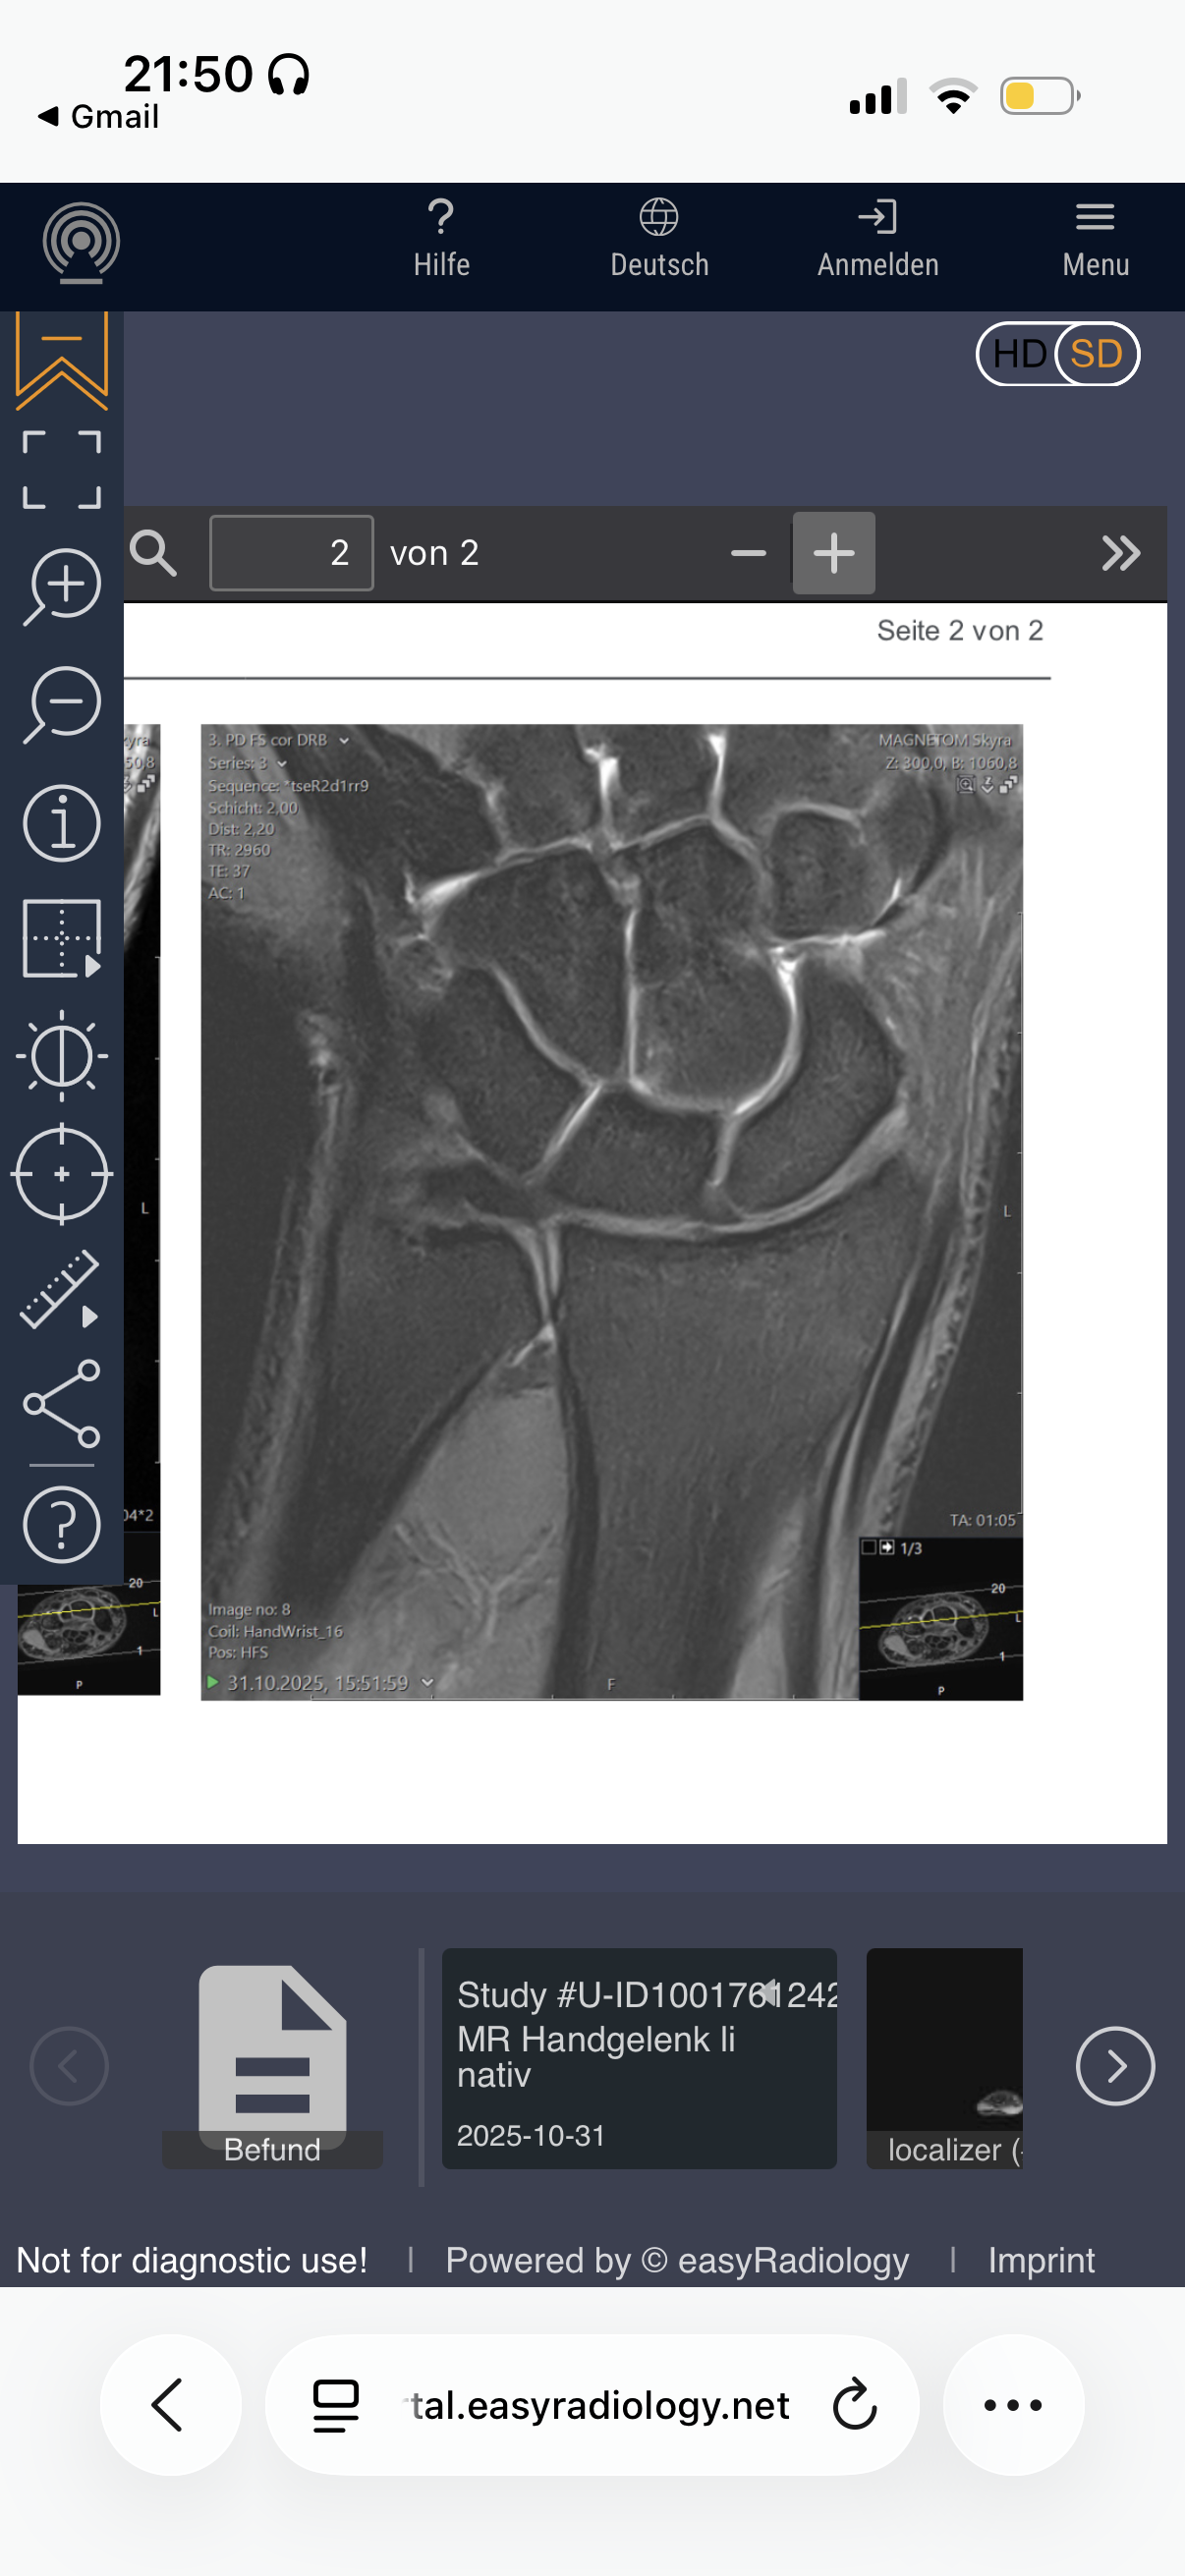

Are my growth plates closed and if not how much growth would hgh + ai help me grow?

Attachments

• IMG_0430.png

IMG_0430.png

Your hands won’t grow, this dosent mean your legs growth plates are closed tho.